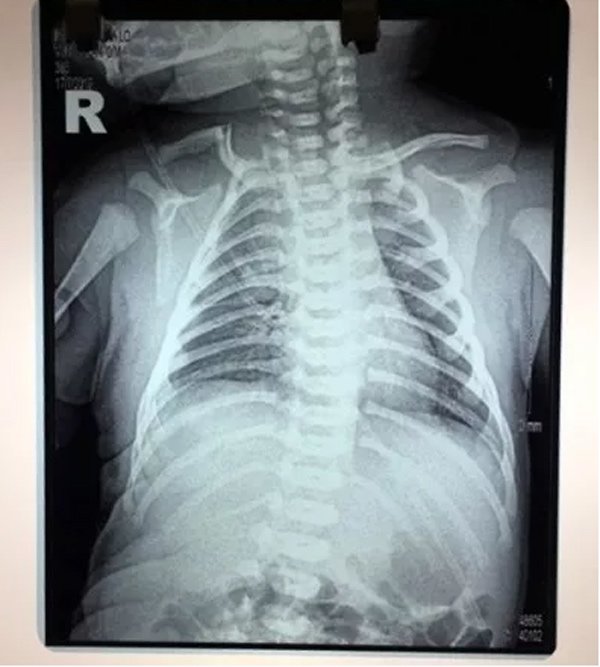

Tại Trung tâm y tế huyện Nghĩa Lộ các bác sĩ sau khi thăm khám, chụp phim và có kết luận: "Em bé bị gãy xương đòn".

Thông tin em bé vừa sinh đã bị gãy xương đòn khiến gia đình anh Tuấn choáng váng. Để yên tâm điều trị cho con, anh Tuấn đã chuyển em bé xuống Bệnh viện nhi Trung Ương để điều trị. Tại Bệnh viện nhi Trung ương, các bác sĩ cũng có chẩn đoán bé Bình An bị "Gãy xương đòn do chấn thương khi sinh".

Hình ảnh X- Quang cho thấy bé Bình An bị gãy xương đòn